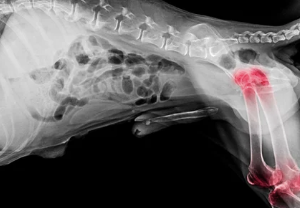

- 사전 검사:

- X-ray나 CT 촬영으로 상태를 확인.